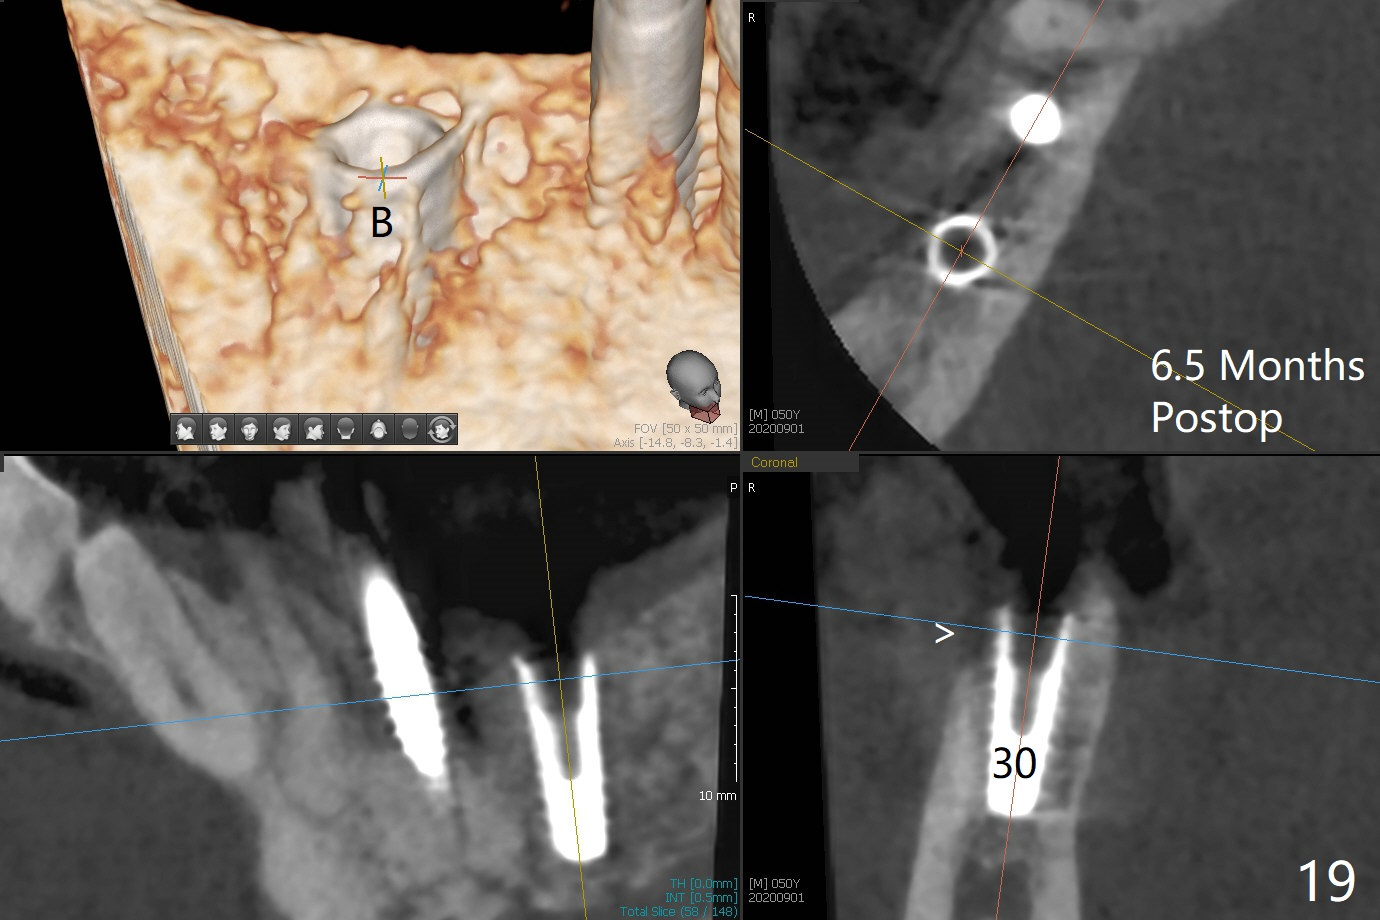

The implant at #30 was also buccally placed (Fig.6,7) and should be corrected in the same manner (Fig.7 green). Due to the bone being harder in the molar region, a smaller and shorter implant (4x11 mm vs. 5x13 mm) shifts slightly buccally while being placed (Fig.8,9). Since primary stability is lower (<20 Ncm vs. 35 Ncm associated with the implant #29), an abutment is not placed, which may be favorable to healing, but it is difficult to achieve primary closure. After bone graft (Fig.9 *) and 2 layers of PRF, Cytoplast is placed. Cytoplast appears to be exposed buccally (Fig.10 <) and occlusally (Fig.11 ^) asymptomatic 9 days postop. Exposure of Cytoplast is more distinct without sign of infection 15 days postop (Fig.12). The patient returns with chief complaint of "foul smell" 7 weeks postop (coronavirus lockdown). Although the Cytoplast exposes more (Fig.13 (* exposed; @ unexposed)), the underlying gingiva remains healthy (Fig.14). While the bone height decreases at #29, the bone density at #30 increases 4.5 months postop (Fig.15). The gingiva heals. The implant at #30 is uncovered 6 months postop. The lingual plate has to be removed for the uncover, while the coronal end of the buccal one is missing. No bone graft is added. When the 4.5x4 mm healing abutment is removed 6.5 months postop, the buccal plate looks concave at #30 (Fig.16' *). The buccal plate looks thin at #29 with a cotton roll placed buccally (Fig.16 R). The lingual plate at #29 is coronal to the buccal one (Fig.17). The buccal gingiva at #29 is quite long (Fig.18). The coronal buccal plate appears to be missing (Fig.19 >), which will be watched. A 4.5x7.5(4) mm cemented abutment is torqued (Fig.20).